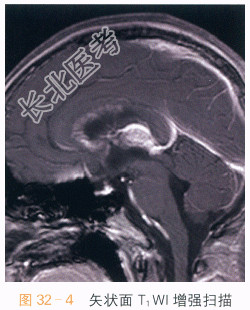

读片分析:头颅横断面T₁WI、T₂WI示松果体区不规则软组织肿块影,呈T₁WI等高、T₂WI低信号影,信号不均匀;横断面、矢状面T₁WI增强扫描可见病灶明显强化,室管膜亦可见明显强化。